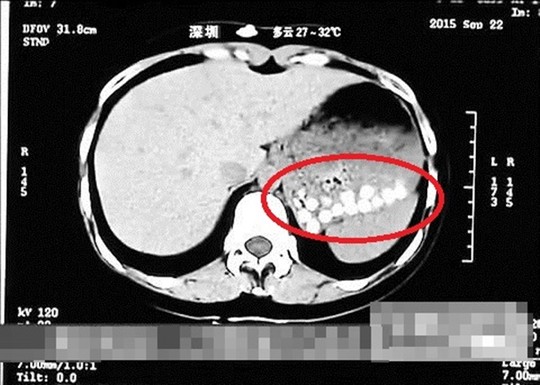

Theo Hong Kong Free Press, một phóng viên tại TP Thanh Đảo, tỉnh Sơn Đông đã uống trà sữa trân châu từ một cửa hàng địa phương. Kết quả CT scan dạ dày của phóng viên này tại bệnh viện cho thấy những viên trân châu dồn lại một chỗ, không thể tiêu hóa được.